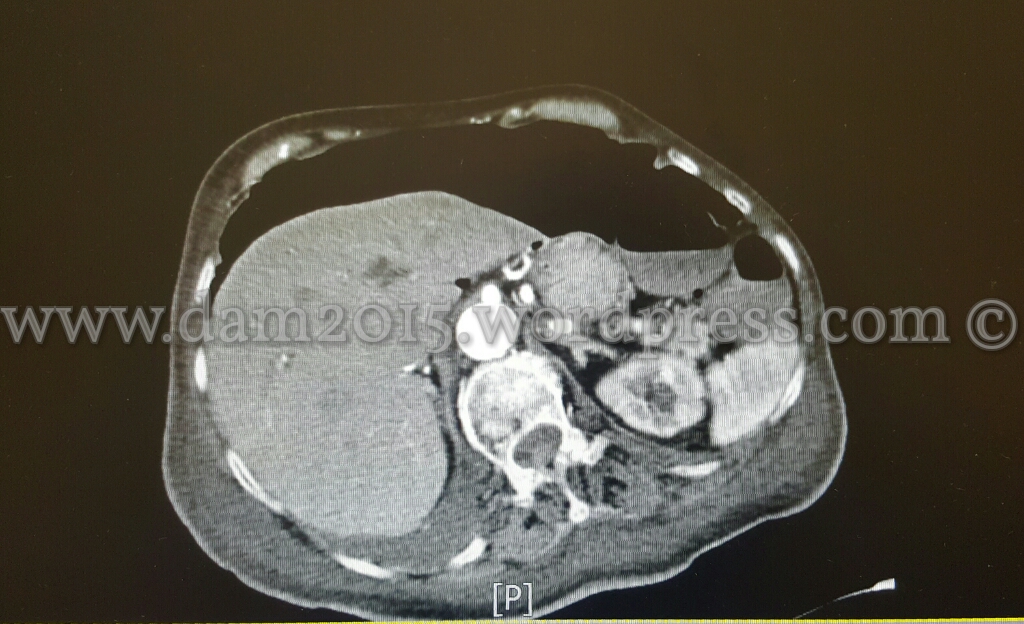

Pz donna, 82 anni.

Malattia oncologica in stadio avanzato.

Eseguita TC addome con MDC che documenta abbondante quota di aria libera in sede sottodiaframmatica come da perforazione di viscere cavo (verosimilmente della parete anteriore del cieco).